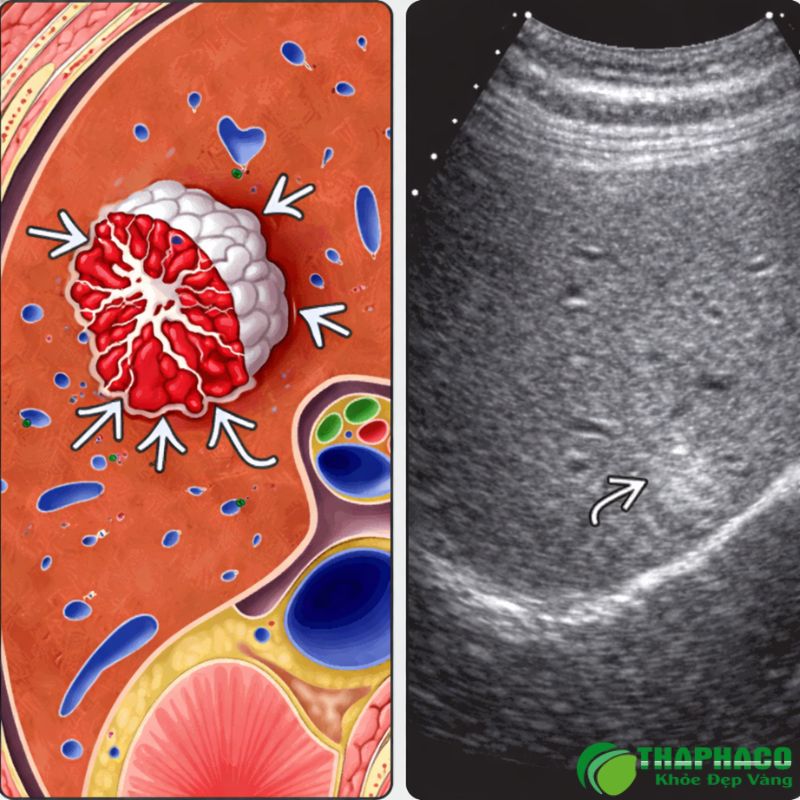

Để chẩn đoán u máu trong gan, các bác sĩ thường sử dụng các phương pháp hình ảnh như:

- Siêu âm gan: Phương pháp đầu tay, đơn giản, không xâm lấn và hiệu quả để phát hiện khối u.

- Chụp cắt lớp vi tính (CT scan) có tiêm thuốc cản quang: Cung cấp hình ảnh chi tiết hơn về kích thước, vị trí và đặc điểm của khối u.

- Chụp cộng hưởng từ (MRI) có tiêm thuốc tương phản: Được coi là tiêu chuẩn vàng trong chẩn đoán, cho phép đánh giá chính xác nhất bản chất của khối u.